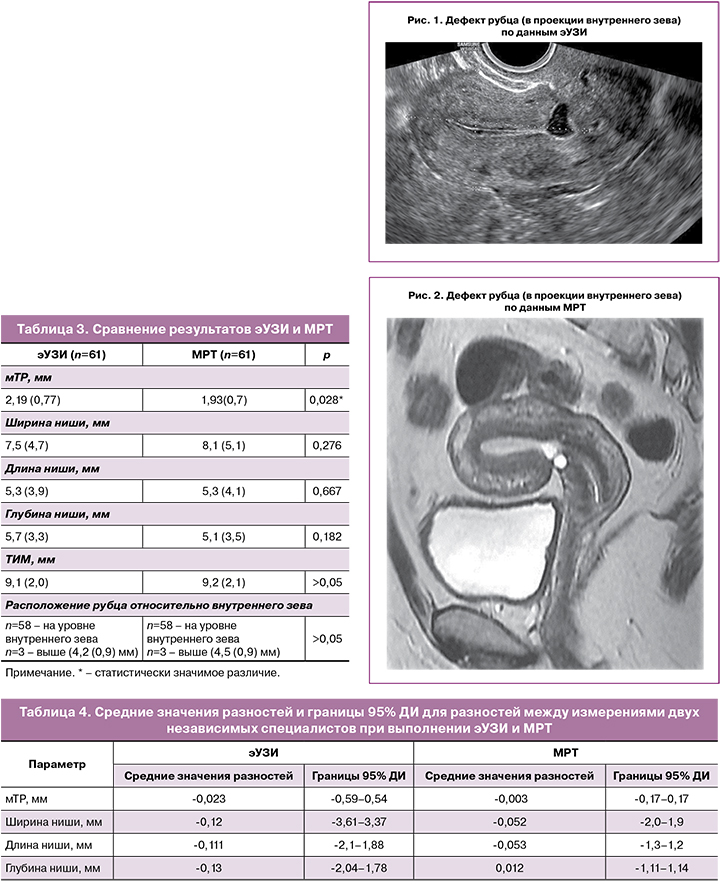

Для сравнения результатов двух методов исследования (эУЗИ и МРТ) был проведен расчет средних значений параметров РМ, полученных двумя независимыми специалистами в каждом методе (табл. 2), и далее проведен сравнительный анализ полученных результатов (табл. 3).

При сравнительном анализе данных эУЗИ и МРТ были выявлены статистически значимые различия при измерении мТР. В свою очередь, различия в измерении ширины, длины и глубины ниши не были статистически значимыми (табл. 3).

По данным эУЗИ и МРТ рубец на матке определялся в области нижней трети передней стенки матки в 3 случаях, а в остальных случаях – в проекции внутреннего зева (рис. 1, 2).

С целью оценки согласованности измерений одних и тех же параметров, полученных двумя специалистами с разным уровнем подготовки в рамках каждого метода исследования (эУЗИ и МРТ), был проведен сравнительный анализ для независимых переменных, который не выявил статистически значимых различий. В связи с этим был использован анализ Блэнда–Альтмана. Были вычислены средние значения разностей между измерениями двух независимых специалистов, а также верхние и нижние границы 95% доверительного интервала (ДИ) для разностей между измерениями двух исследователей в рамках каждого метода (табл. 4). Чем ближе к «0» были расположены средние значения разностей и чем меньше была ширина 95% ДИ, тем более однородными являлись измерения.

При анализе графиков Блэнда–Альтмана было выявлено, что средняя разность между значениями, полученными первым и вторым исследователем, как при эУЗИ, так и при МРТ, была приближена к 0, что свидетельствовало о хорошей согласованности измерений. Однако в большей степени обращал на себя внимание тот факт, что разности между результатами, полученными при эУЗИ, имели более широкий 95% ДИ по сравнению с данными, полученными при МРТ, что свидетельствовало о бóльшем разбросе результатов при выполнении эУЗИ и, соответственно, более выраженной согласованности и однородности результатов при использовании МРТ.